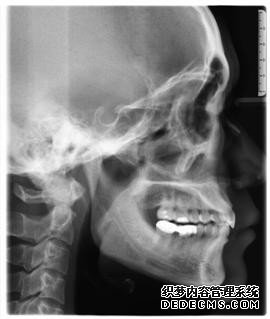

临床诊断:通过3D数字化全景机的检查,患者的上牙前突属于牙性,双唇闭合时可见明显隆起,X片显示根尖无异常,上下后牙存在间隙,可通过美国MBT直弓丝正畸技术将其矫正复位,并收拢间隙,矫正所需时间一年半左右。

全景机侧位片